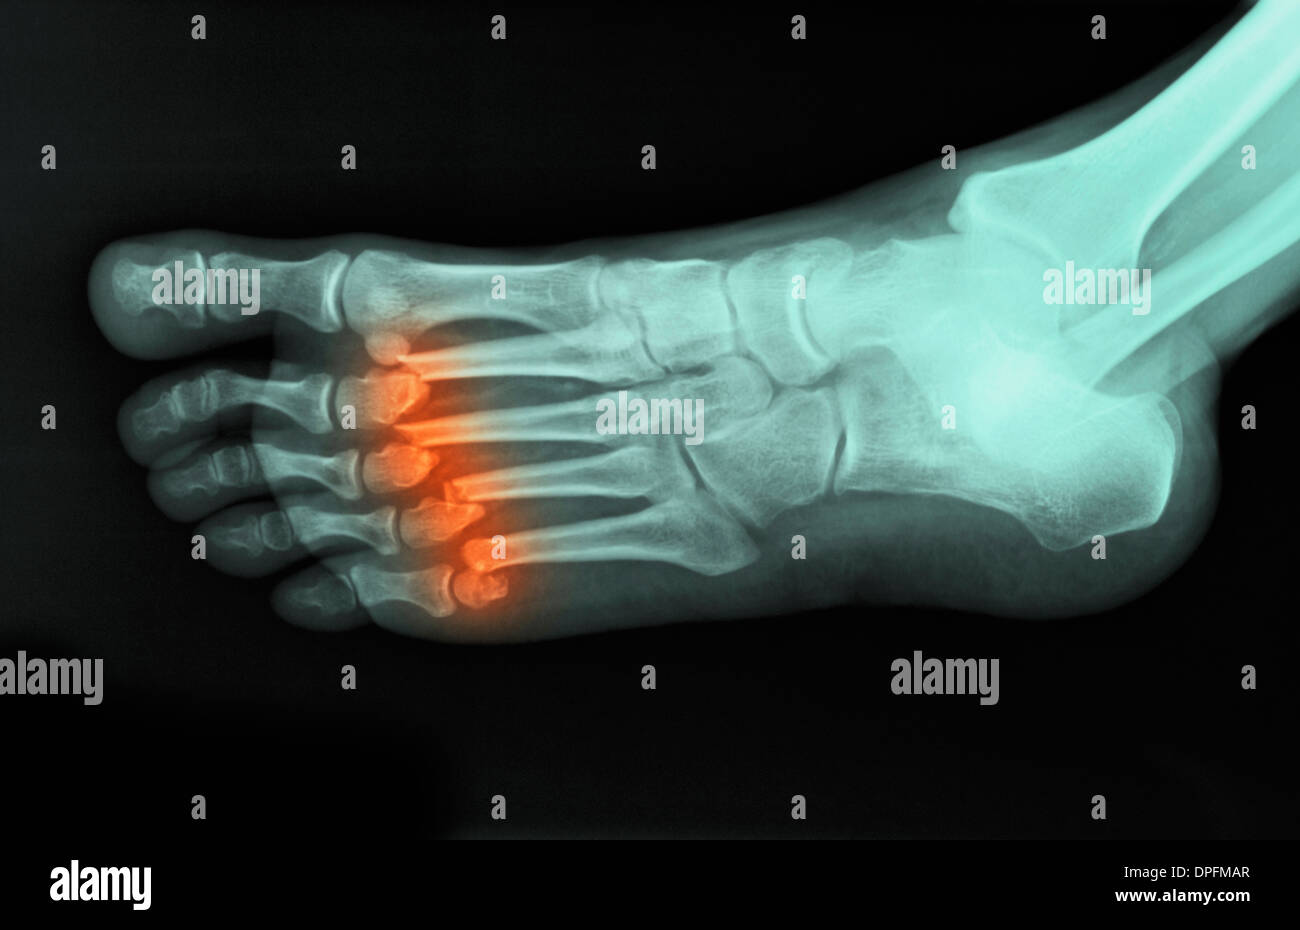

xray of foot showing fractured metatarsals Stock Photo Alamy X Ray Of Fracture Foot You can also break a bone through overuse or repetitive stress on. A broken foot bone might cause some of these symptoms: Foot radiography is required if there is pain in the midfoot zone and any of the following: Sports injuries, accidents and falls can all lead to a broken foot. Bone tenderness at point c (base of. Pain that. X Ray Of Fracture Foot.

Fractured metatarsal foot bones, Xray Stock Image C038/6652 Science Photo Library X Ray Of Fracture Foot Sports injuries, accidents and falls can all lead to a broken foot. Foot radiography is required if there is pain in the midfoot zone and any of the following: Fractures and dislocations of the forefoot (metatarsals and phalanges) are usually straightforward to identify, so long as. You can also break a bone through overuse or repetitive stress on. A broken. X Ray Of Fracture Foot.